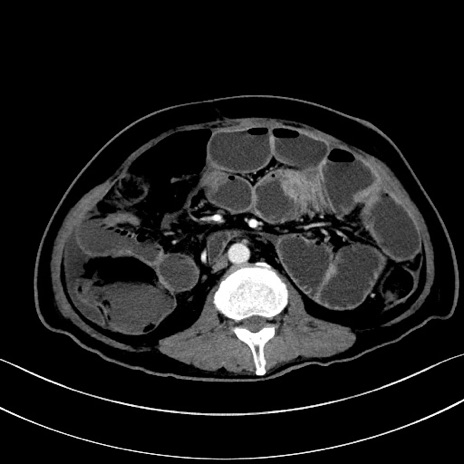

症例28(横断像)

【症例】60歳代男性

【主訴】嘔吐

【現病歴】胃癌にて胃全摘後。食思不振が悪化し、夜中に嘔吐することがある。

【既往歴】胃癌、胃全摘、脾摘、胆摘後

【データ】WBC 5900、CRP 10.56